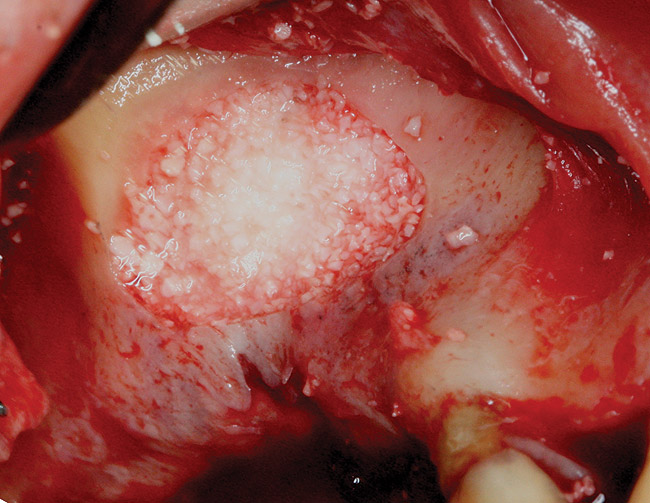

The technique described below is based on a deep buccal full-thickness flap with vertical release in the canine area, followed by creation of a “window” at the lateral wall of the sinus (Figure 2). The bony window is either removed or rotated medially with the sinus membrane and pushed inward. The Schneiderian membrane is then separated from the bone anteriorly, posteriorly, and medially until clinically sufficient space is established (Figure 3). The created space, which occupies the lower third of the sinus, is filled with a bone graft (Figure 4), and the lateral access window is covered with a collagen membrane (Figure 5).

Fig 4. Space is created between the Schneiderian membrane and the sinus walls filled with particulate xenograft.

Figure 4